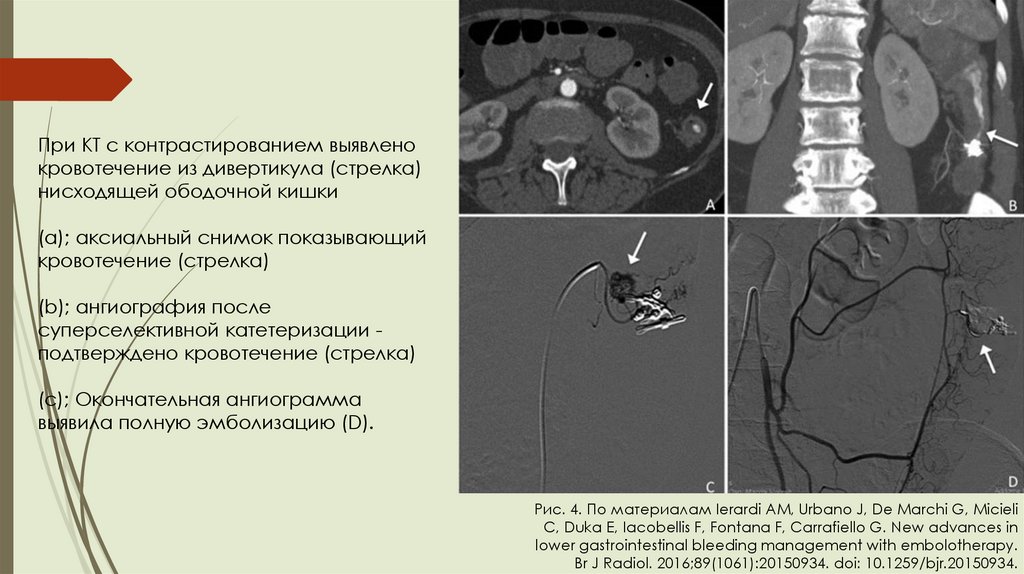

Диагностика и лечение:

Колоноскопия – позволяет определить

источник и провести лечебные

мероприятия: (инъекция адреналина

рядом с сосудистым дефектом,

лигирование). (Рис. 3).

МСКТ-ангиография – если

нестабильная гемодинамика не

позволяет применить колоноскопию.

Позволяет применить метод

транскатетерной эмболизации. (Рис.

4).

При КТ с контрастированием выявлено

кровотечение из дивертикула (стрелка)

нисходящей ободочной кишки

(а); аксиальный снимок показывающий

кровотечение (стрелка)

(b); ангиография после

суперселективной катетеризации подтверждено кровотечение (стрелка)

(с); Окончательная ангиограмма

выявила полную эмболизацию (D).

Рис. 4. По материалам Ierardi AM, Urbano J, De Marchi G, Micieli

C, Duka E, Iacobellis F, Fontana F, Carrafiello G. New advances in

lower gastrointestinal bleeding management with embolotherapy.

Br J Radiol. 2016;89(1061):20150934. doi: 10.1259/bjr.20150934.